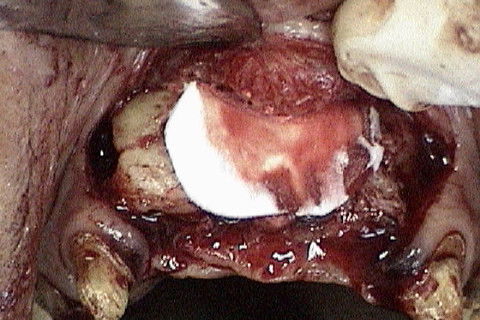

Mostrando o defeito ósseo após rebatimento do retalho

Bloco ósseo cortico-medular

Bloco ósseo sendo fixado com o auxilio de pinça porta-enxerto

Blocos ósseos fixados. Os espaços entre os blocos foram preenchidos com osso particulado. Na verdade deveriam ser utilizados 2 blocos nessa região e não somente 1 como foi utilizado.